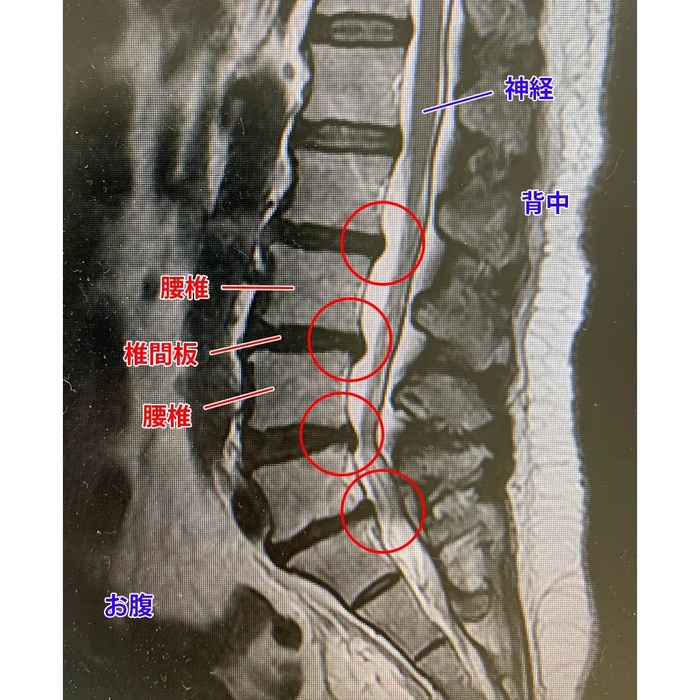

通过腰椎核磁确认到从第2节到第5节椎间盘全都变形。椎间盘突出、椎间盘退变。导致椎间盘周围发炎,炎症一直持续,是导致慢性腰痛以及神经症状的原因。另外支配腿脚的神经也部分受压伴有椎管狭窄症。

检查了4节椎间盘(L2/L3、L3/L4、L4/L5、L5/S1),确认全部破裂,随后做了DST修复再生术。从管控室看手术室的情形。医疗翻译陪在患者身旁, 手术全程帮助翻译沟通。